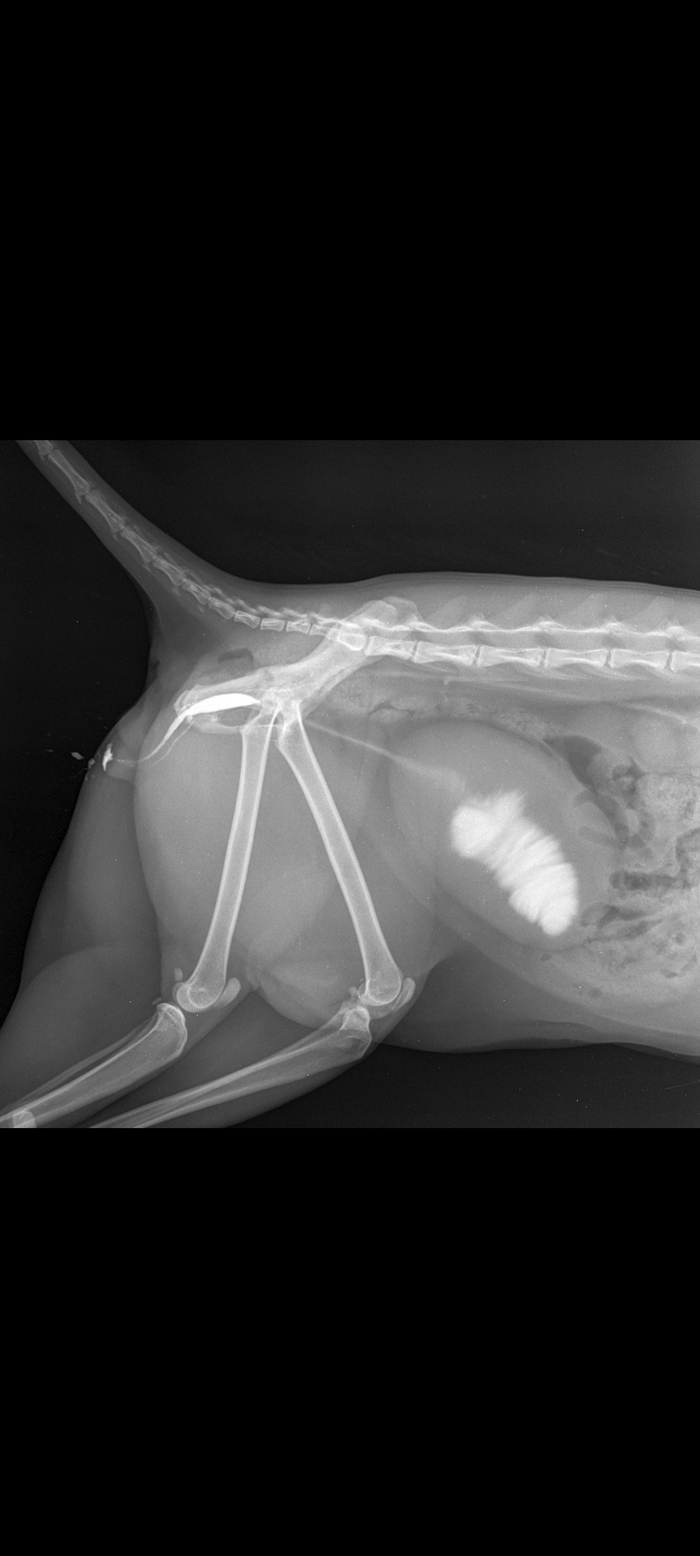

Сходили к врачу, обследовали, сдали анализы мочи, анализ крови, на инфекции. Инфекций ВИК, ВЛК не выявлено.

Сделали УЗИ в мочевом пузыре обнаружили песок, признаки МКБ.

В моче обнаружили кокки и струвиты. Необходимо одно из лекарств: Уро-Урси, Милоджик или Уро-Про.

Сидя в клетке, кот заработал себе цистит и МКБ (мочекаменную болезнь).